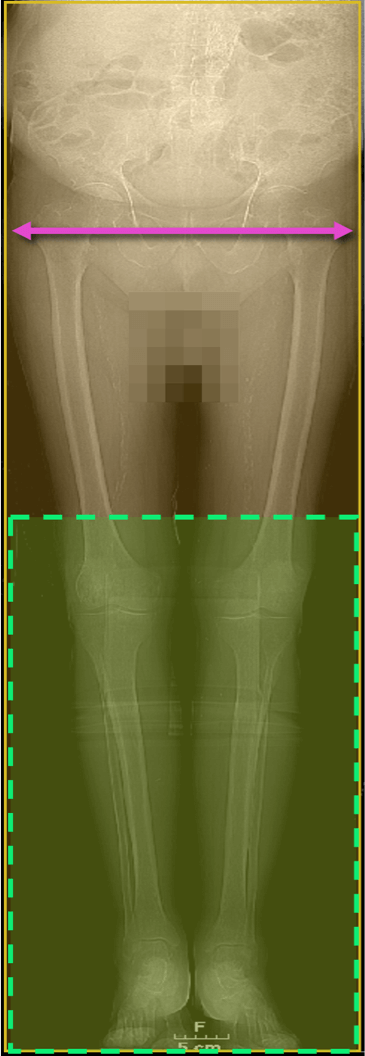

Reconstruct thin slice images (e.g. 1.0 mm slice thickness at 0.7 reconstruction interval) with reconstructed field-of-view from trochanter to trochanter on scout image to improve pixel resolution.

Peripheral CTA Scan Acquisition / Recon1

Scanning Range 1

Celiac artery (~T12) toes: (105 – 130 cm)

Scanning Range 2

Above the knees > toes

Always pre-programmed, but only initiated by RT if no contrast in pedal vessels

Reconstructions

Thin, overlapped

FOV = greater trochanters